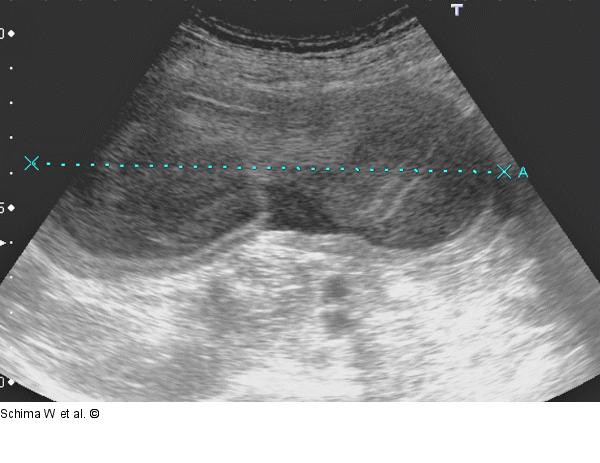

Abbildung 1: Sonographie Die Sonographie zeigt eine große, tubuläre zystoide Raumforderung im rechten Unterbauch. Die Raumforderung ist dickwandig, der Inhalt ist nicht echofrei, wie bei seröser Flüssigkeit einer simplen Zyste zu erwarten wäre. |

Die Sonographie zeigt eine große, tubuläre zystoide Raumforderung im rechten Unterbauch. Die Raumforderung ist dickwandig, der Inhalt ist nicht echofrei, wie bei seröser Flüssigkeit einer simplen Zyste zu erwarten wäre. |